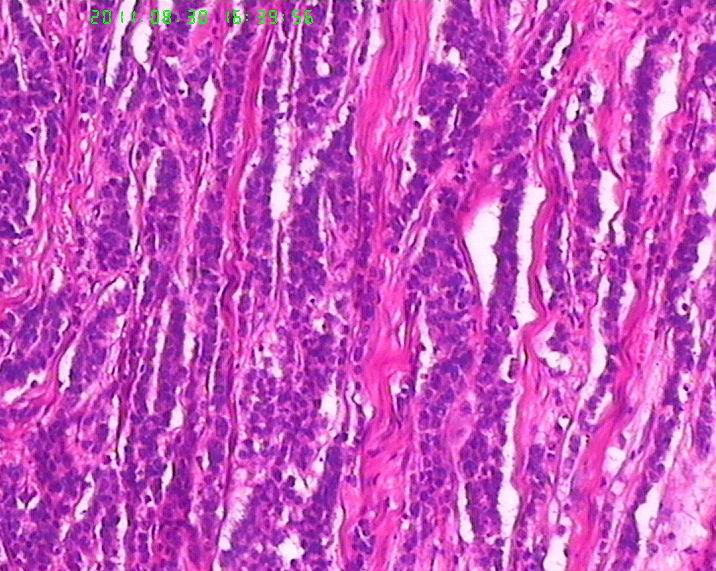

• 焦急:胃肿物,请老师帮看下。图2

图2

肿瘤呈流水线样排列,有腺样结构,核分裂像多见,从这些来说至少不是类癌了,如果是神经内分泌肿瘤,那也应该是神经内分泌癌了,此例可能为腺癌伴神经内分泌分化,需做免疫标记证实是否有神经内分泌分化。

若诊断管状腺癌,其中未见任何“管腺”形成迹象,故应诊断为“未分化腺癌”。但学生有以下疑问:1、为何肿瘤与正常胃粘膜交界处不见“非典型增生腺体”移行,而是截然交界。交界处可见淋巴细胞浸润。2、为何肿瘤浸润肌层的界面圆顿,如同“疣状癌”的膨胀性推挤生长。3、未分化腺癌恶性程度高,而为何胃周淋巴结检出二十余枚均未见转移。

细胞排列器官样,细胞核染色质较细腻,第一考虑类癌,第二除外低分化腺癌.加染IHC最后定类型.